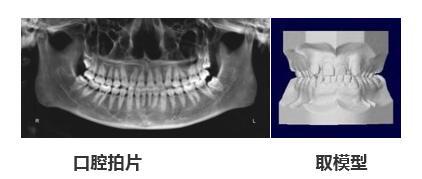

514x248 - 20KB - JPEG